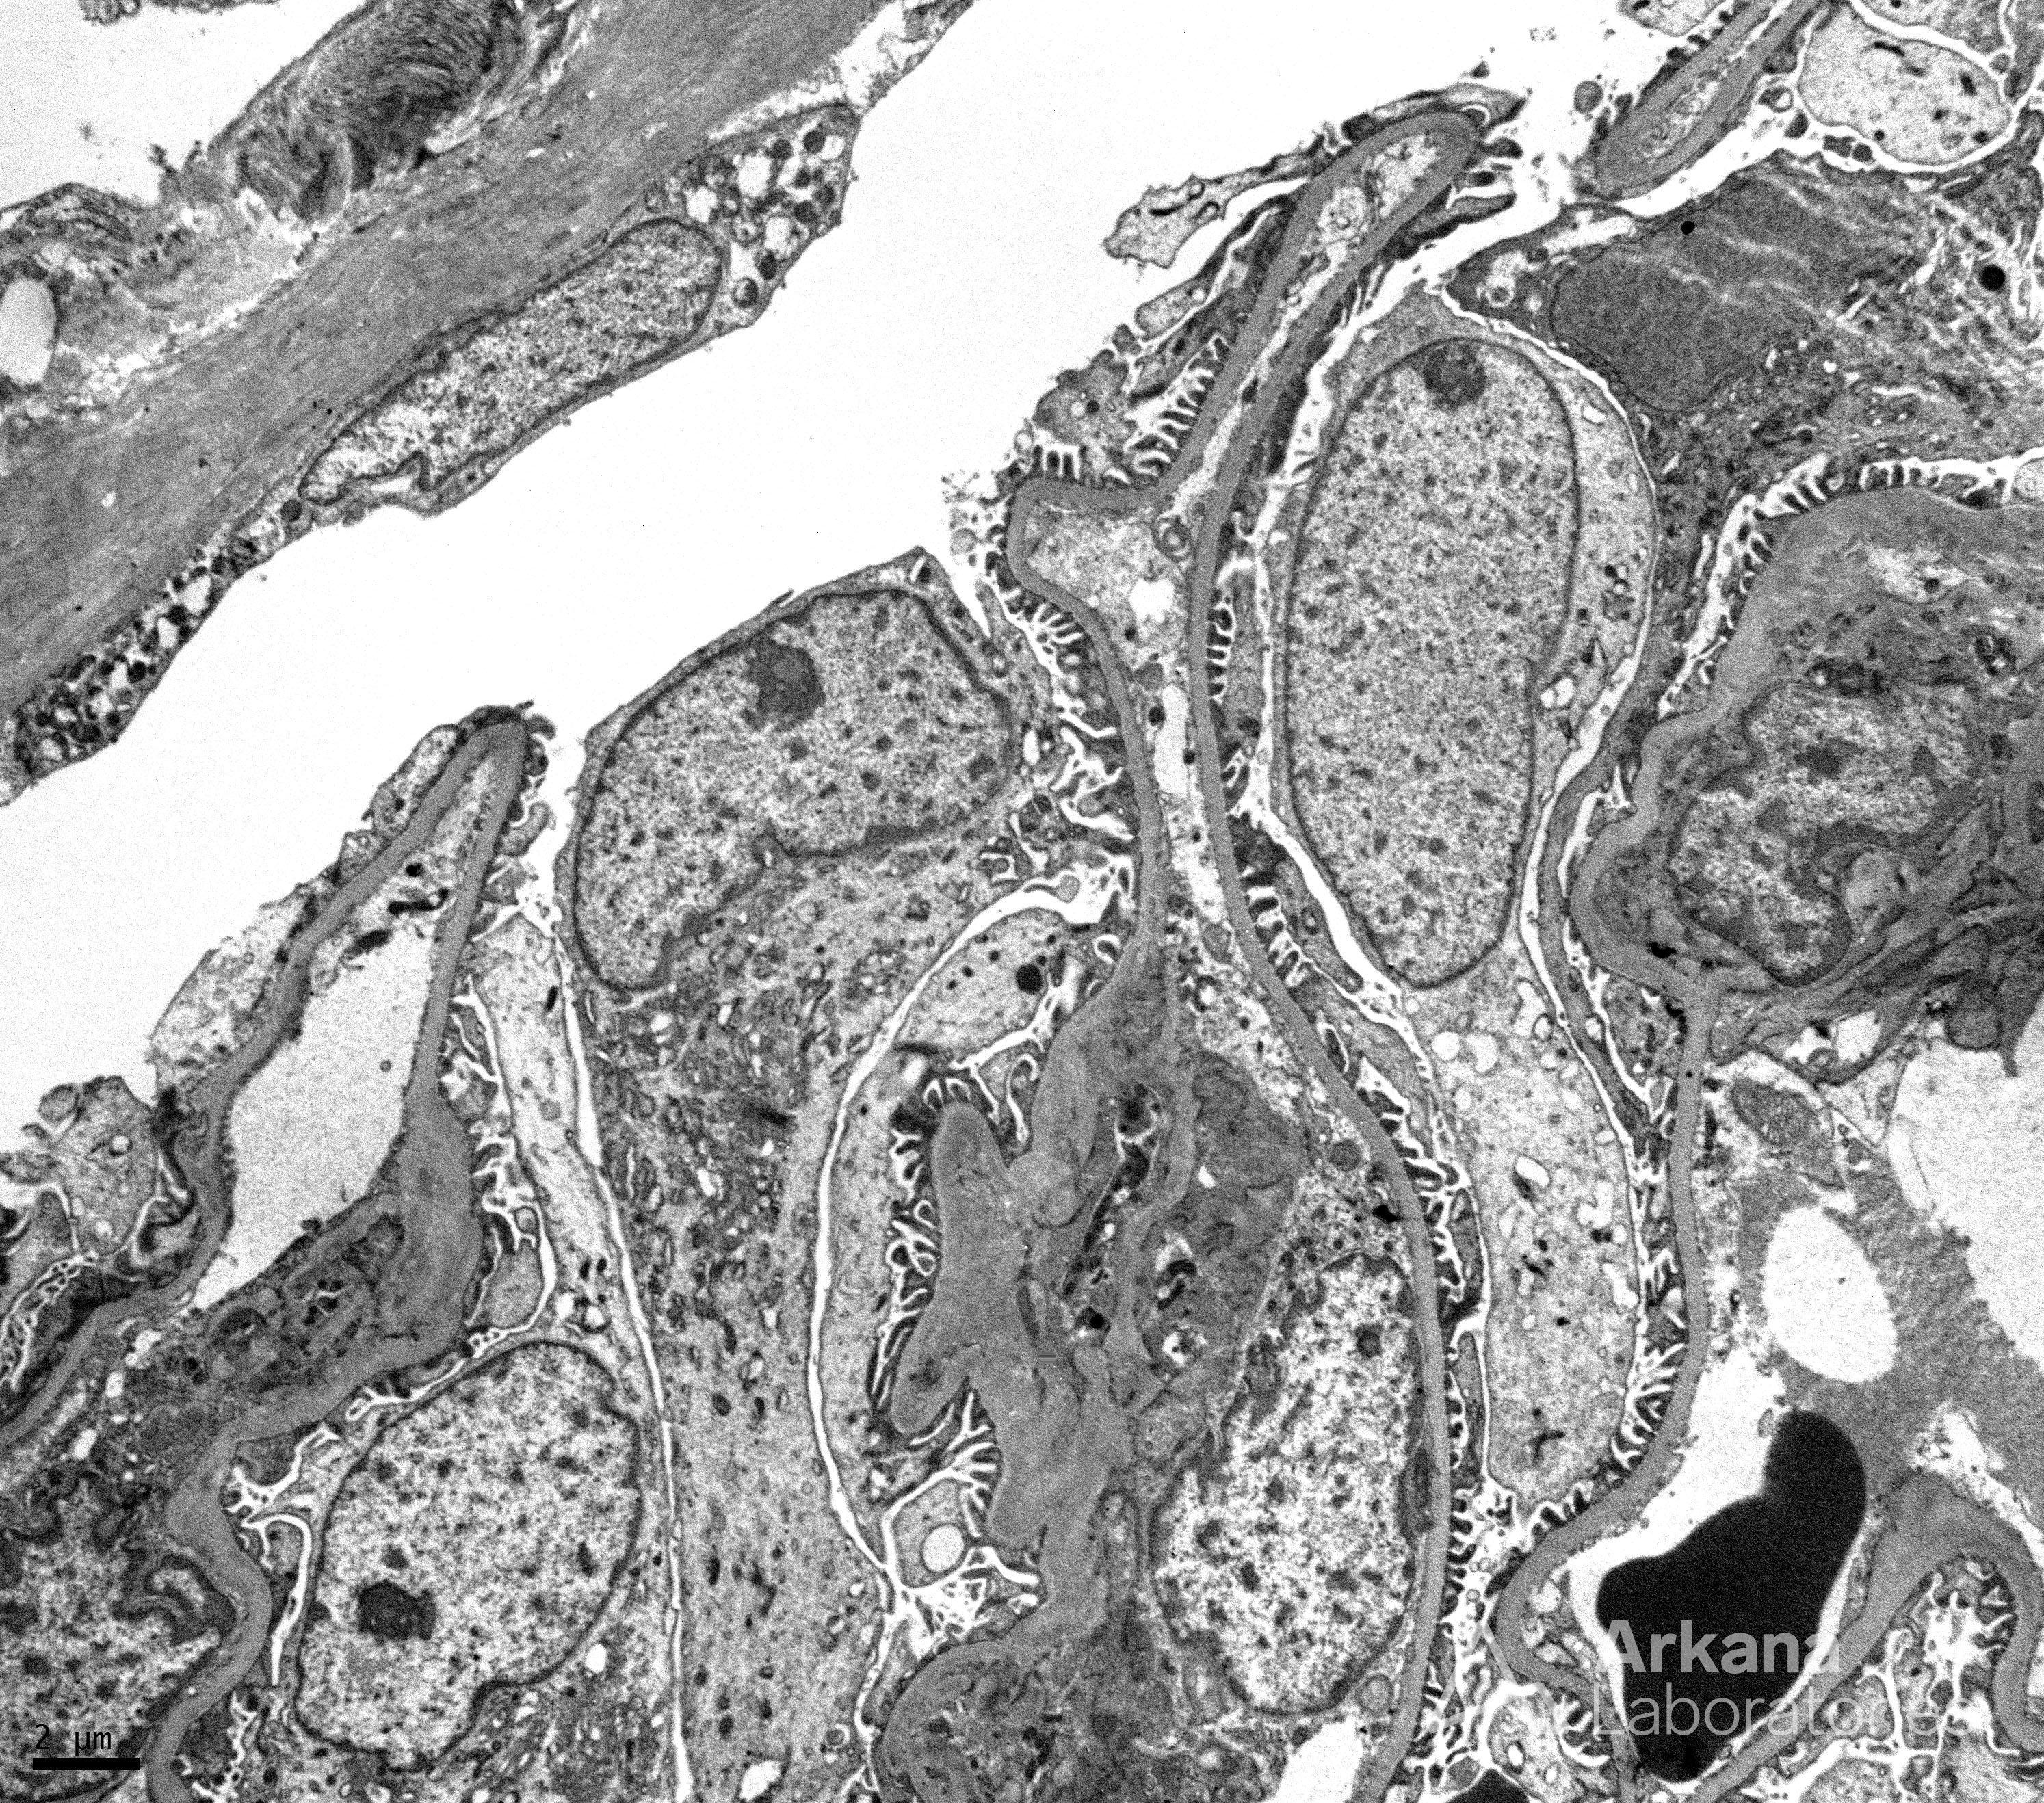

Normal GBMs, Podocytes and Foot Processes